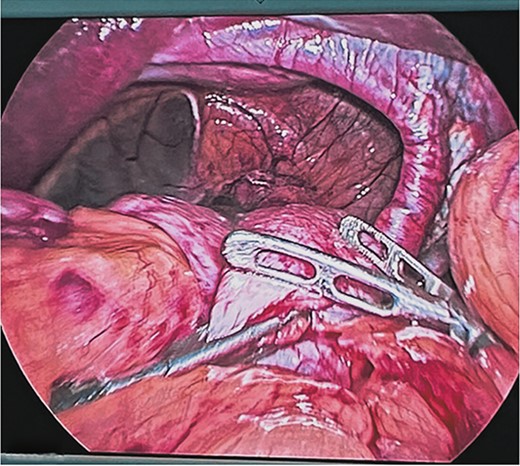

Surgical treatment was decided. Five ports were used: one supraumbilical 12 mm port for the telescope, one 5 mm subxiphoid port for the liver retractor, and three working ports placed in the left midclavicular line of 12 mm, the left axillary line of 5 mm, and the right midclavicular line of 5 mm. A type IV hiatal hernia was found with a 12 cm hernia defect (Fig. 3), a hernia sac measuring 20 cm × 15 cm × 7 cm, containing the entire stomach, dudodenum, pancreas, greater omentum, and transverse colon. The content was reduced to subsequently dissect and resect the hernia sac (Fig. 4).

Reduction of the contents of the hernial sac with intestinal forceps and blunt dissection. Hiatal defect of ~12 cm.